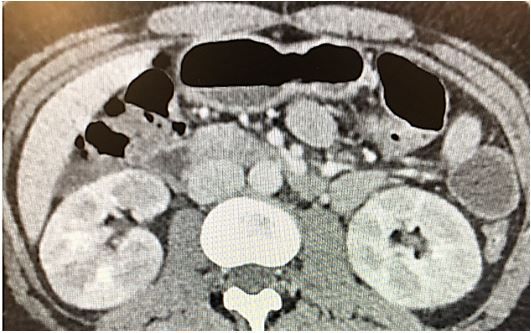

Imaging: a CT scan is done, results below.

Image: Abdominal CT scan